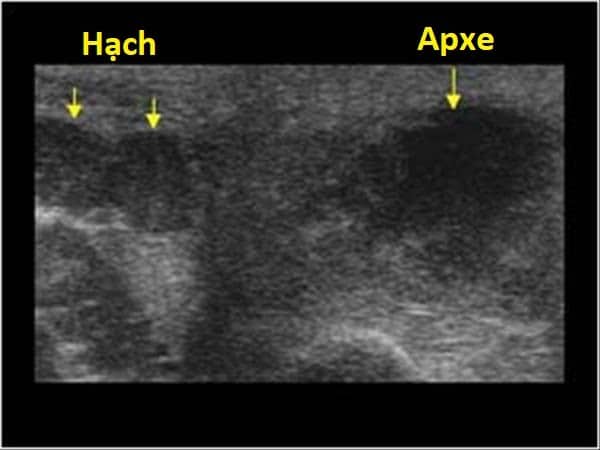

» Thông tin: Nam giới – 36 tuổi.

» Lâm sàng: Sưng đau vùng mang tai.

# Viêm tuyến nước bọt mang tai apxe hóa / Tăng kích thước hạch vùng cổ.